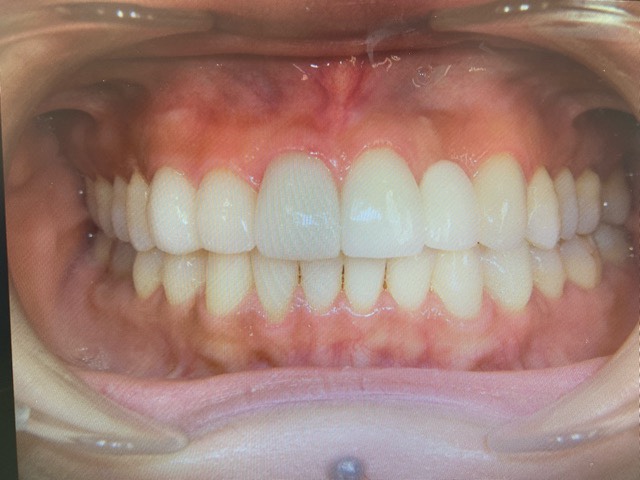

下の歯はインビザライン矯正を行い、上の歯はセラミッククラウンで治療させていただきました!

下の歯のガタガタや、歯の隙間 いわゆるブラックトライアングルも綺麗に治り、

上の歯の曲がった部分も、高さの違っていた歯肉の位置も、綺麗に整っているのがお分かりになると思います。

この歯並びですと、日々のお手入れも楽に出来ますし、綺麗な歯並びの美しい笑顔は、何よりの宝物です。